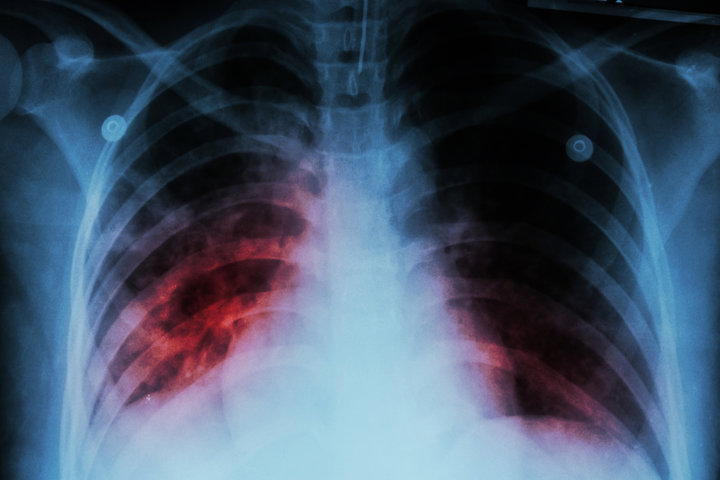

결핵은 전염성이 강한 감염병으로, 특히 집단시설과 의료 환경에서는 예방이 필수적입니다. 결핵 예방을 위해 다음과 같은 조치가 필요합니다.